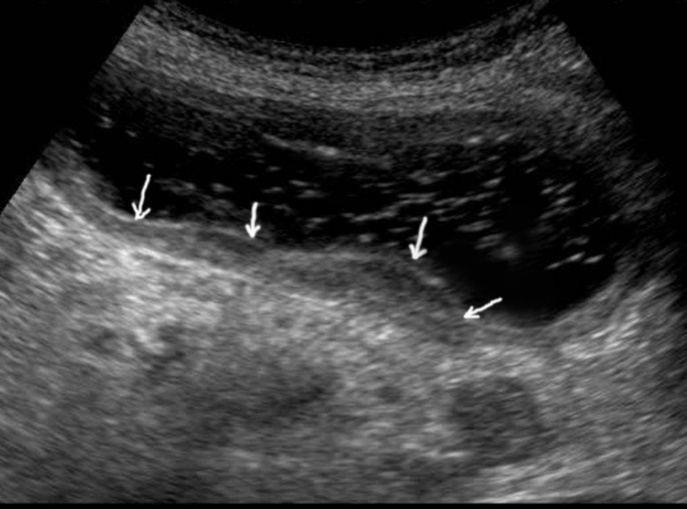

T3 stage of polypoid form was recorded in one case, ulcerative form – in 11 cases, infiltrative ulcerative forms – in 21 cases and diffused infiltrative forms – in 8 cases. The Sonographic features of infiltrative ulcerative form of gastric carcinoma was shown as local uneven thickening of the stomach wall with a length of up to several centimeters with intermittent images and ulceration of the mucosa (Figure 11). The Ulcerative form of gastric carcinoma was shown as a raised margins surrounded by a thickened gastric wall with irregular margins (Figure 12). Gastric carcinomas of diffuse infiltrative form is illustrated as a diffuse thickening of the muscle layer, a smooth contour, discontinuous mucosal image without ulceration and involvement of the serous membrane in the process (Figure 13).

Figure 13.Gastric carcinomas of diffuse infiltrative form in the posterior wall of the stomach body of stage T3. The tumor is manifested by diffuse thickening of the muscle layer, a smooth contour, discontinuous mucosal image without ulceration and involvement of the serous membrane in the process. An enlarged, altered lymph node of low echogenicity, round shape, without differentiation of the peripheral and central part, is visualized behind the stomach.